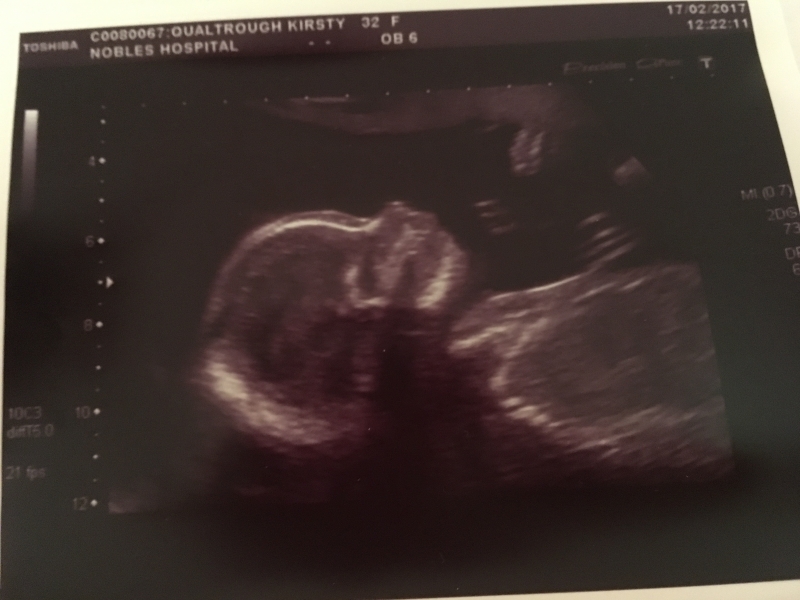

I thought it was time to add a new blog post to bring things up to date as it's been quite busy since the last post in early Feb! I'm now working for Ellan Vannin Chiropractic Clinic as a Chiropractic Assistant (basically receptionist/cleaner), with shifts on a Wed and Thurs morning in Douglas and a Friday afternoon in Ramsey. It's been really good to have a bit of routine and have a role that's really social...only issue is I have to stand for most of the shift (5-6 hours) so not sure how long I'll be able to keep that up! We had our 20 week scan on 17th Feb - it was a relief (and also still a bit scary and completely overwhelming) to see the little one was progressing as it should. Since then I felt my first rumbles and kicks, and now at 23 weeks I'm feeling kicks every day (normally at night after tea), Glenn's also felt them and we've even seen the kicks happening on my tum! Crazy to think what's going on, and that it's a completely natural process that I don't have any control over! So what with the pregnancy progressing it was time for us to seriously think about moving into a bigger place. We decided south would be the best location given that once baby is here I'll be based at home full-time, and as we currently only have the one car it makes sense (and would be nice!) to be near Mum and friends. So we spent a few weekends viewing properties in PE and PSM...some newer builds (Erin Crescent in PE, Creggan Lea in PSM) and also a few older properties (bungalows in Ballamaddrell) but nothing fitted the bill. However, we then heard about a bungalow up Ballakillowey that had been up for rent for ages but had not been lived in and the landlord was willing to negotiate on price. It was so different from anything we'd seen and fitted (most) of our criteria in terms of space, garden, homely. It was a bit neglected having been left for so long however it certainly had more character than anything else we'd seen. So, after negotiating with the agency (Harmony Homes) we secured a year let on 6 Viking Close 🙂 The start of March was busy with packing up and cleaning the flat (wasn't that sad to say goodbye!) and moving south to Colby 🙂 It hasn't quite been plain sailing with the house so far - we've had issues with the heating and washing machine and are still waiting for the hot water pressure to be sorted (it doesn't help that the landlord is based in Norway so nothing happens quickly) however, we already feel settled in and are both really happy we've made the move. Although Glenn's got a bit more of a commute now I think this was the best time to move as it's given us plenty of time to iron out any issues and get settled in ourselves before the little one arrives 🙂 I've already taken advantage of the patio and been sitting out whenever the sun shows itself! This week has mainly been more unpacking and getting bits sorted for the house. Jam, Don and the girls popped up at the weekend..Mum's currently away in Norway on a cruise with her friends Margaret and Tony. After initially being without her luggage as it was 'misplaced' by the coach company she's now enjoying the sights and -2 temperature!) I've now got midwife appointments every month and need to look into aquanatal and pregnancy yoga classes now that I'm starting to get bigger...anything that'll help keep me active, pain-free and potentially help with labour day is top of the list! We're also contemplating booking a 'pre-baby' holiday to have one last relax away from work etc before life changes forever so watch this space for updates! 🙂 Below are a few photos of the last month.